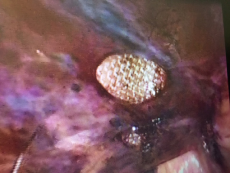

Contrast-enhanced CT was not done as the condition was very obvious clinically. He was taken up for diagnostic laparoscopy under general anesthesia which showed herniation of distal small bowel loop through a peritoneal defect of the previous hernioplasty site with dense adhesions of the bowel to the mesh .The herniated bowel was reduced, the hernia defect was dealt with closure by direct stitching and glue again of the mesh to the abdominal wall after aspiration of the reactionary fluid, stitching itself was not an easy task because of the friability and thinness of the peritoneal flap and this is why a glue is used. The patient had an uneventful recovery and was discharged on the fourth post-operative day. The patient underwent follow-up examination 21 days after discharge and did not have any significant abnormality.1–3

Figure 3 Small bowel herniation through the peritoneal flap defect